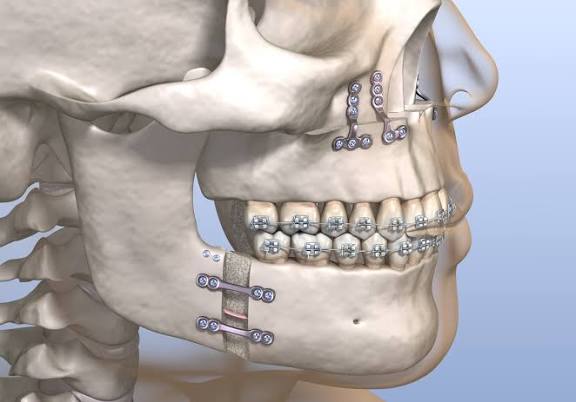

It cut the bone Whose name is an osteotomy

And it advance it

View attachment 4590079